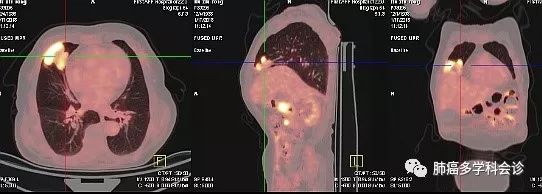

PET-CT示:1.十二指肠降部局部肠壁稍增厚代谢活跃,右肺中叶软组织肿块代谢活跃,考虑恶性病变;右侧顶叶及左侧顶枕叶多个稍高密度结节代谢活跃,腹腔多发肿大淋巴结代谢活跃,T4左侧附件骨质破坏伴软组织肿块代谢活跃,右侧大收肌内低密度团块影代谢活跃,考虑转移。2.右侧结肠旁沟内软组织结节代谢较活跃,考虑良性病变可能。3.右侧丘脑及双侧基底节区软化灶;双侧筛窦及上颌窦炎症。

3.jpg行CT引导下肺占位穿刺活检,病理示:(肺穿刺活检)考虑肿瘤性病变;补做免疫组化后出第二次报告:间变大细胞淋巴瘤,ALK阳性。